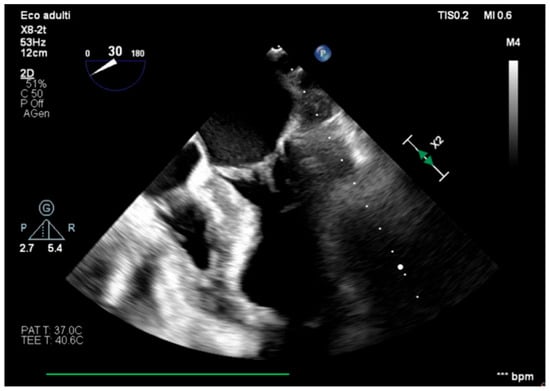

The transesophageal echocardiography showed LVOT-VTI 10 cm; apical, septal, and anterior wall akinesia; preserved function of the medium-basal segments of the inferior and lateral walls (Figure 3, Figure 4 and Figure 5); and RV-FAC 39% with an unloaded right ventricle (Figure 6).

Figure 4. Long-axis view, improved function of the inferior–lateral wall.